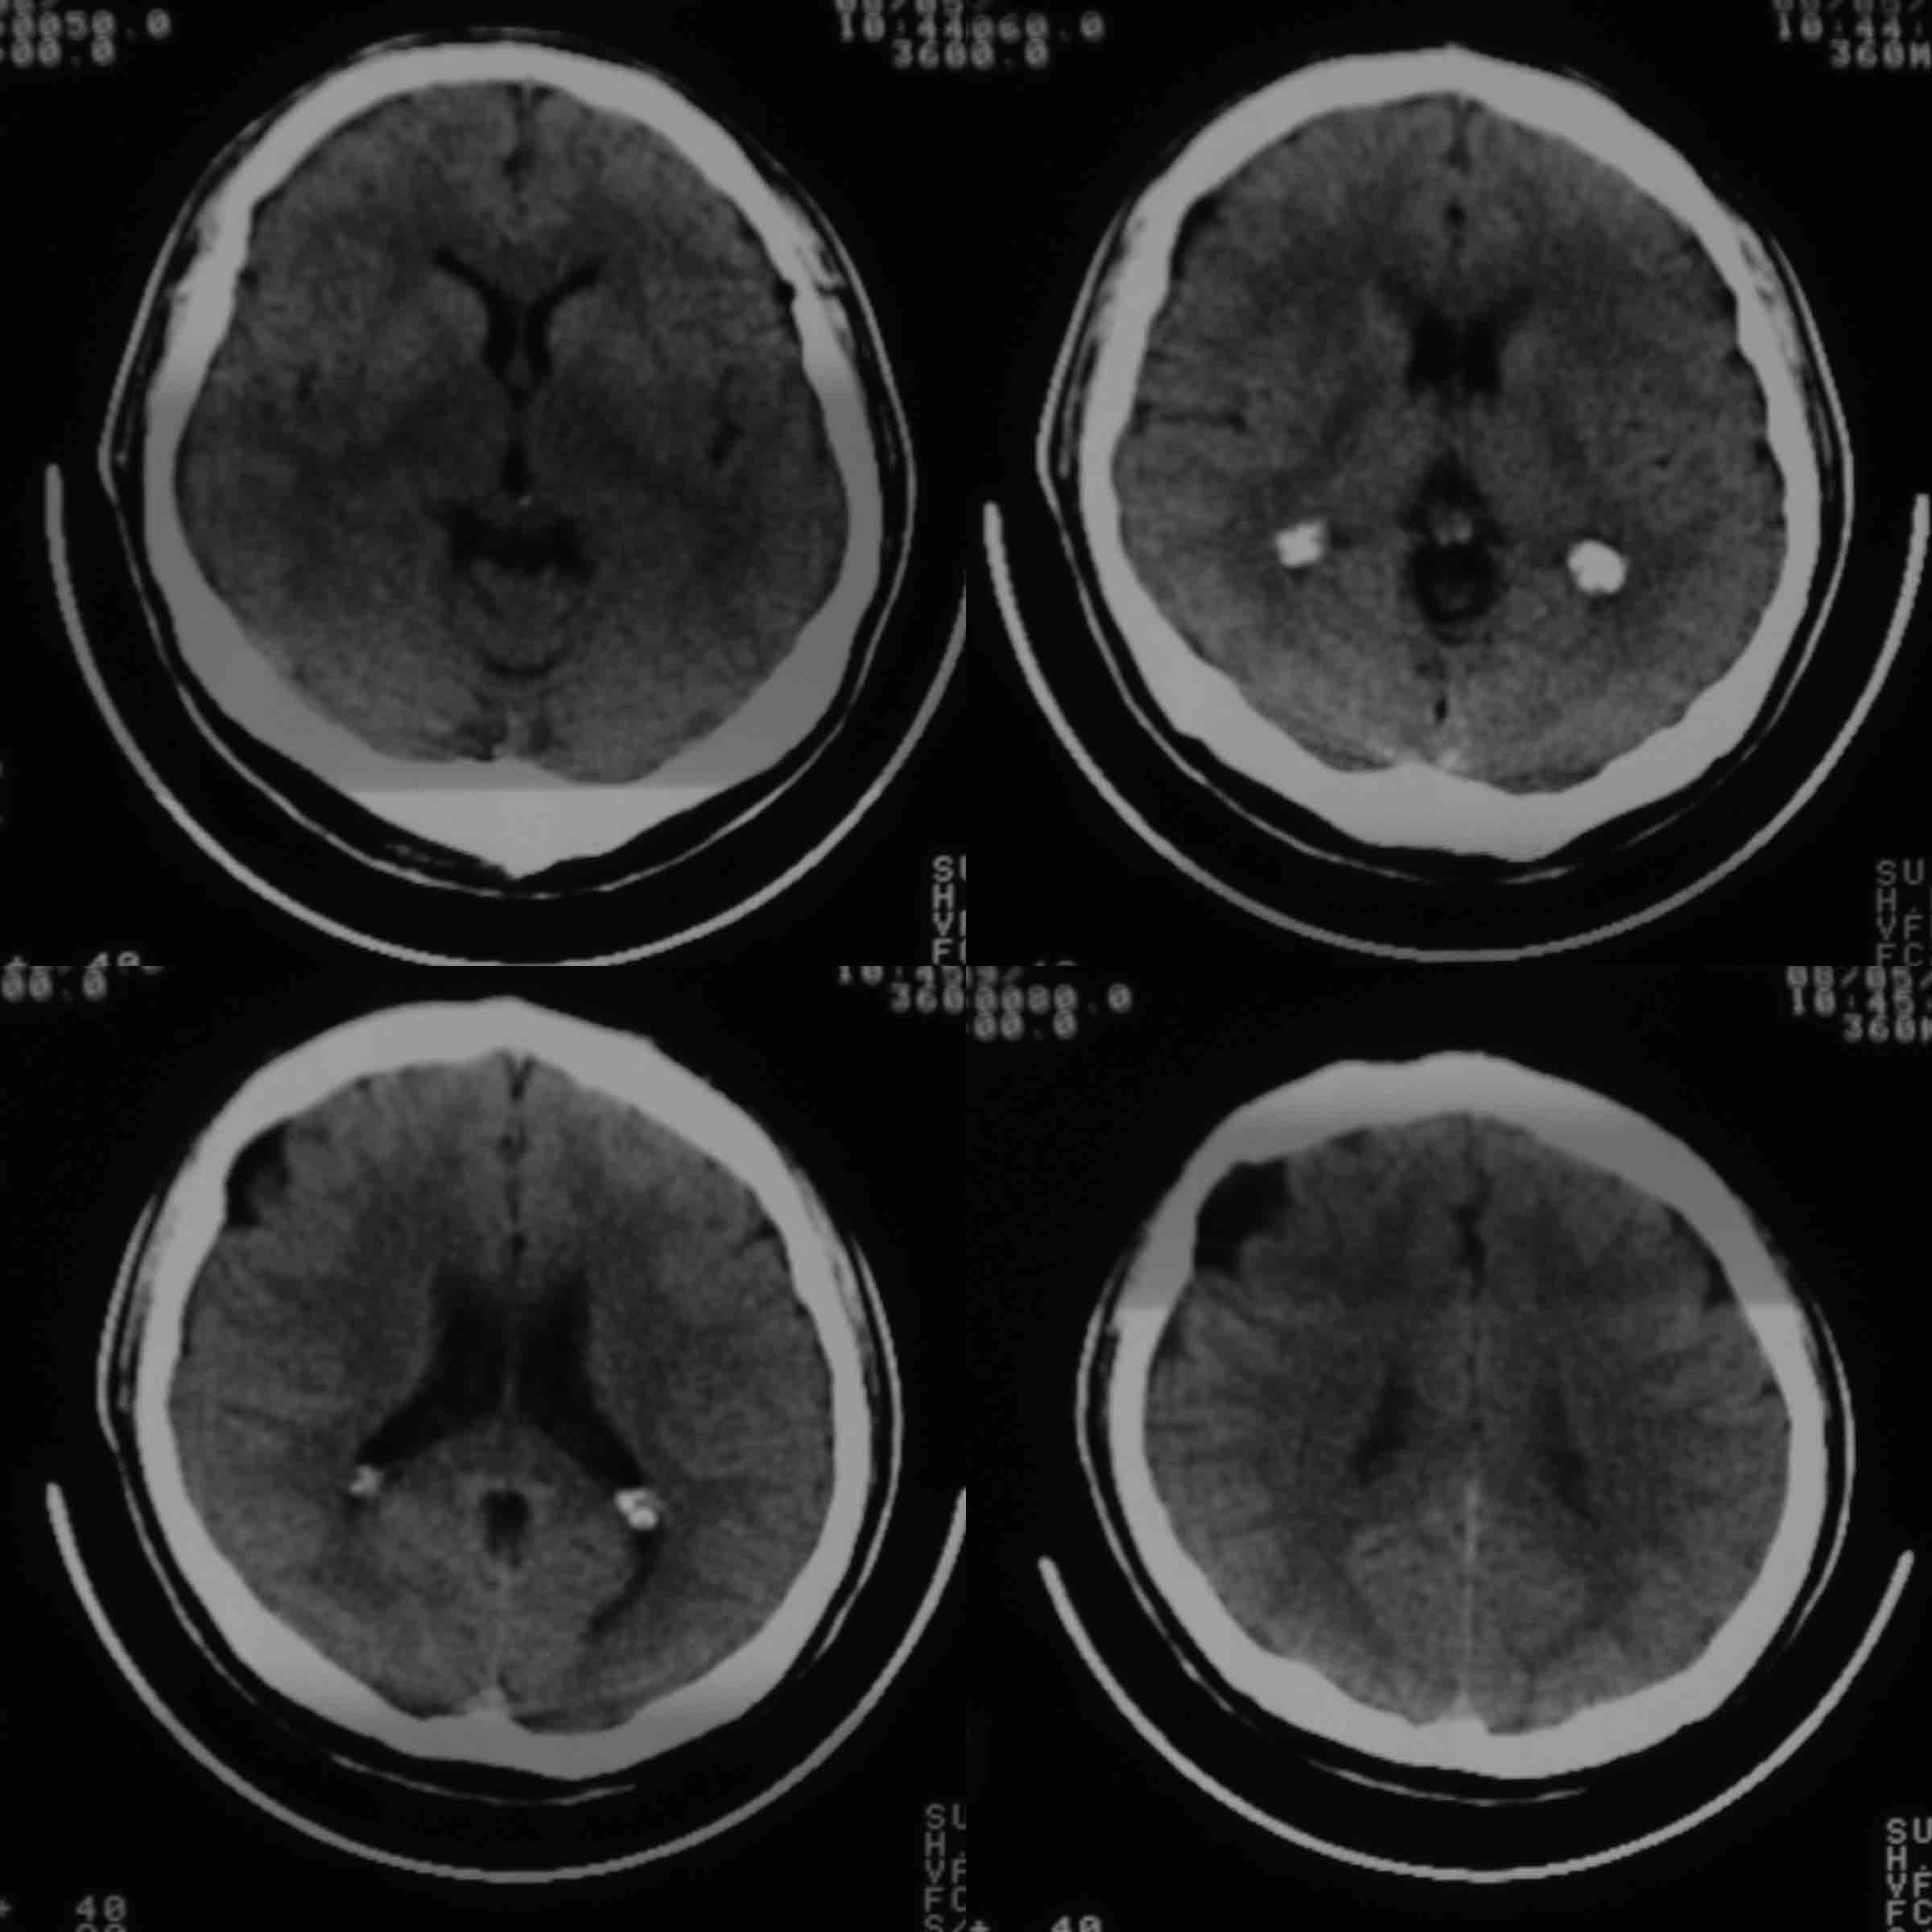

男37岁头持续性痛1天。右额部蛛网膜下腔囊肿诊断是否正确,请老师们帮忙看看。谢谢!

支持右额区蛛网膜囊肿。

有顶叶蛛网膜下腔囊肿

右侧额叶蛛网膜囊肿。